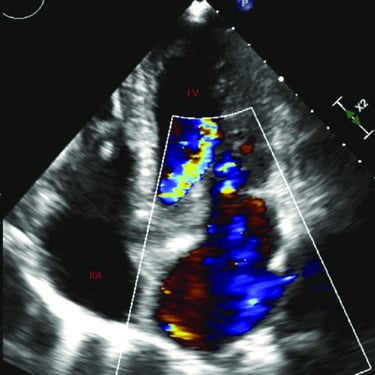

Transthoracic Echocardiogram

An echocardiogram is an ultrasound scan that uses sound waves to create detailed images of the heart, assessing its structure, function, and blood flow to diagnose various cardiac conditions.